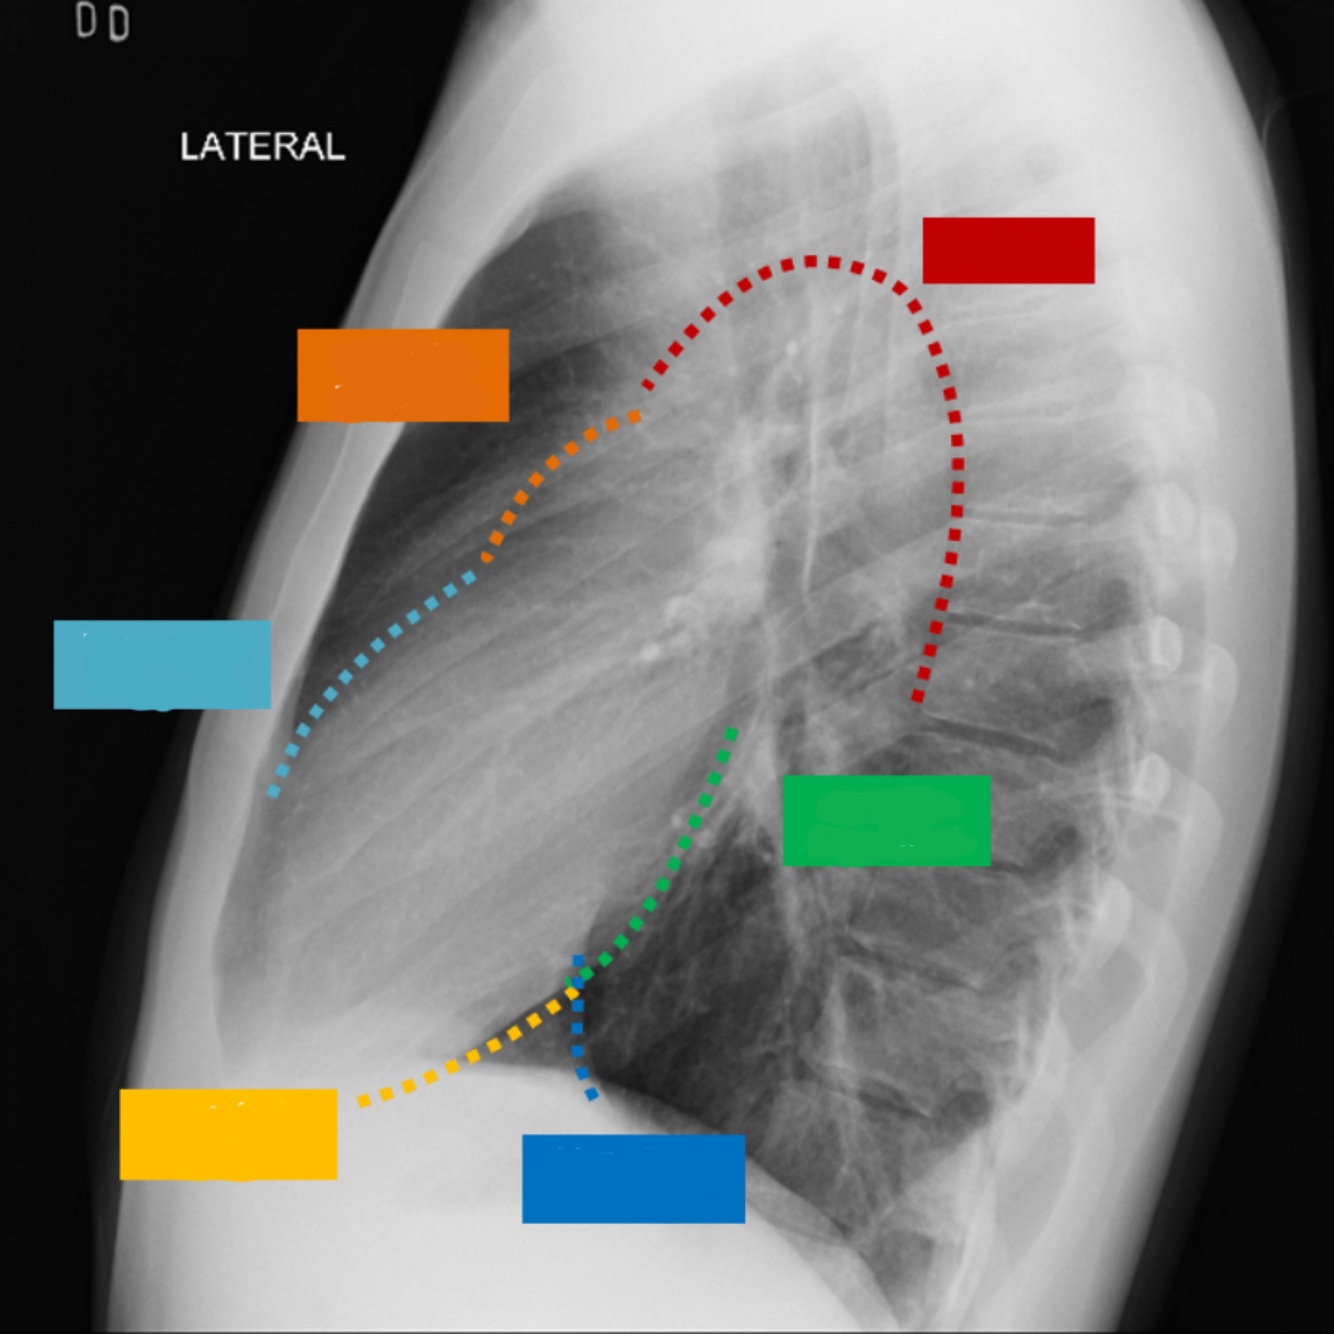

14

Q

•Paciente en posición recta

• Lado afectado sobre el registro

•Brazos levantados por encima de la cabeza

• Mentón hacia arriba

Posición lateral verdadera

* Rayo Central; perpendicular, dirigido a región

torácica media a nivel de 17

(8-10cms por debajo de la escotadura yugular)

¿Que proyección se desea obtener?

A

Proyección lateral